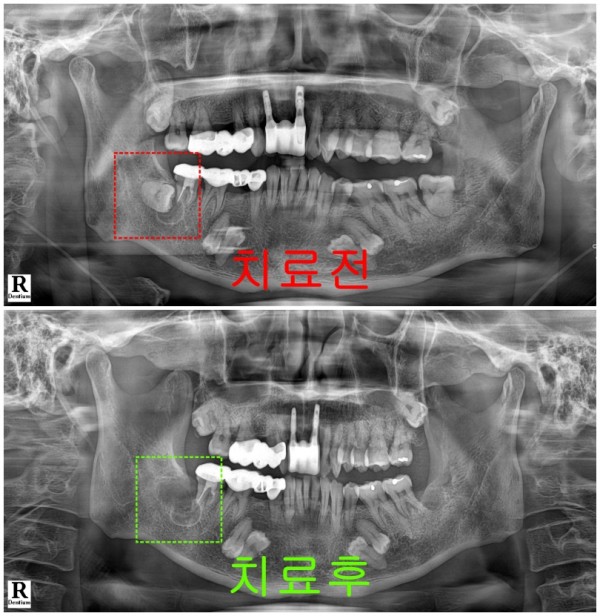

오늘은 48번 사랑니에 발생한 함치성 낭종을

성공적으로 치료한 사례를 통해

이 질환에 대해 자세히 말씀드리려고 합니다.

이번 환자 분의 경우,

48번 사랑니 부위에 꽤 큰 낭종이 자리 잡고 있었는데,

가장 까다로운 점은 바로 하치조신경관과의 거리였습니다.

하치조신경관은 아래턱 뼈 속을 지나가는 신경과 혈관이 들어있는 통로

이곳에 손상이 가면 입술이나 턱 부위에 감각 마비가 올 수 있어서

굉장히 조심스럽게 접근해야 하는 부위입니다.